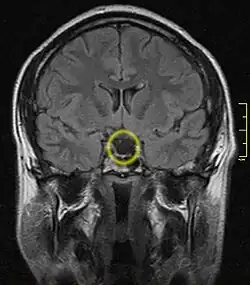

Empty sella turcica on MRI as seen in severe cases of Sheehan's syndrome

MRI is useful in diagnosing Sheehan's syndrome since it examines the structure of the pituitary and may identify any anatomical damage.[5] MRI findings will vary based on how early or late in the disease process the test is being conducted. If an MRI is conducted early enough in the disease process the pituitary may appear larger than normal, and show changes that are consistent with damage from lack of blood supply.[16] Later in the disease process of this syndrome the damage imposed on the pituitary gland will cause it to shrink, and leave a partially empty or totally empty sella turcica on MRI.[8]